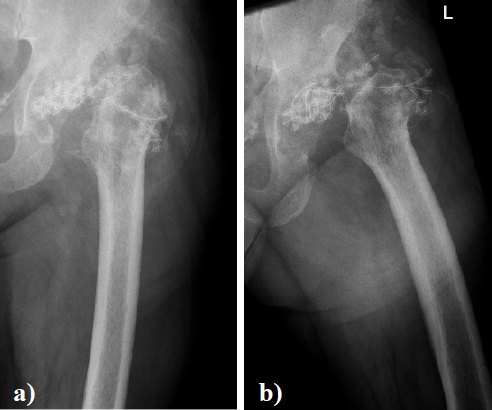

Una típica fractura bilateral de fémur: Presentación de caso.